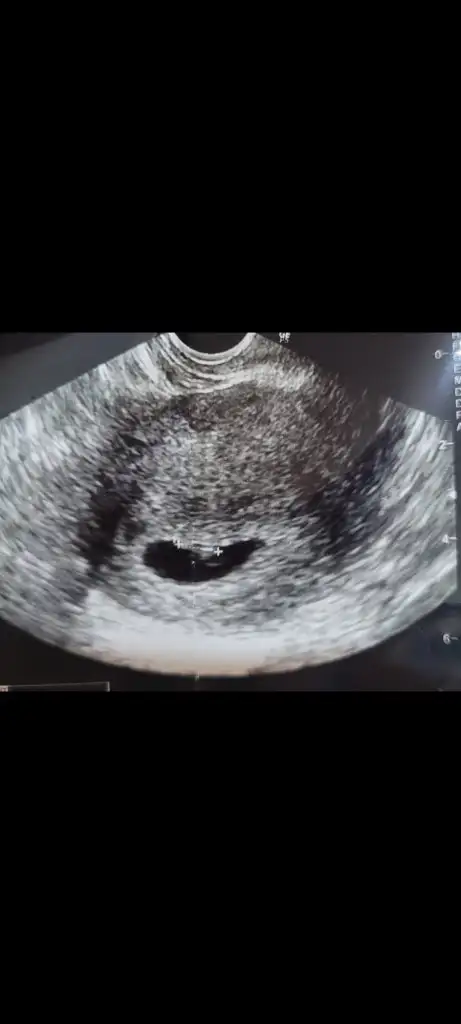

Çok teşekkür ederim.🥰 Eller kollar hareketlenmiş bir de. Öyle görünce içim kıpır kıpır oldu.Bir kızım var bir de oğlum olsun isterim.Ama kız olursa da cok mutlu olurum.Gercekten hiç fark etmez. Evlat sonuçta Rabbim hayırlısı neyse sağlıklı bir şekilde onu nasip eder inşallah.Kızıma hamileyken rüyamda kız olacağını görmüştüm.Bunda bebek gördüm ama cinsiyetini görmedim.@lolaylty 6+1 ve 7+1 ultrason görüntüsüne göre erkek demişti siz de kız dediniz.Hangisi olacak bakalım 😄 Hayırlısı olsun.Rabbim sizin bebeğinizi de gönlünüze göre sağlıklı bir sekilde kucağınıza almayı nasip eder inşallah.🙏💞